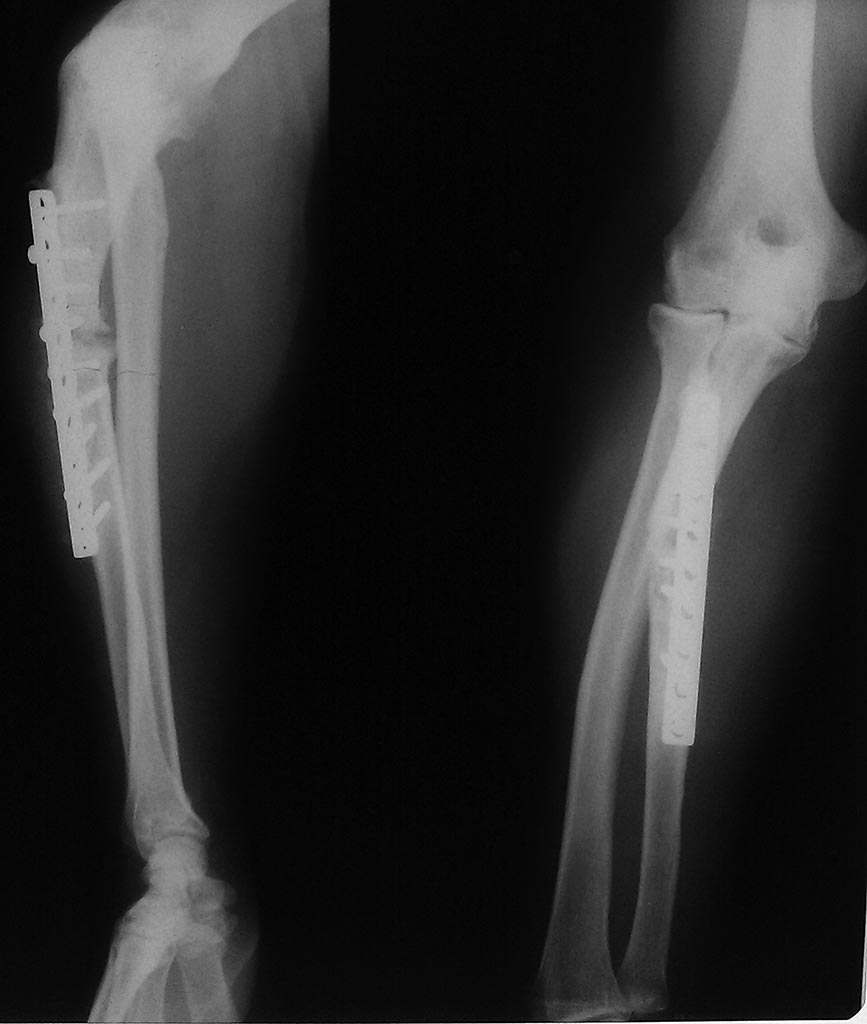

Прошу прощения за качество снимков, все что прислали на консультацию...